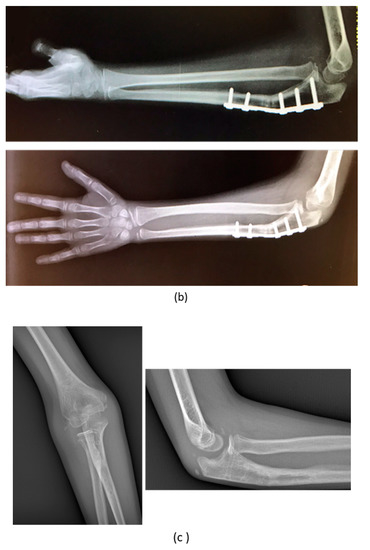

| 1 | F, 9 | Missed Monteggia Lesion | Post-traumatic | Proximal ulnar osteotomy stabilized with a 6-holes plate | None | Corrected |

| 3 | M, 15 | Post-traumatic forearm malunion deformity | Post-traumatic | Bifocal osteotomy stabilized with 1/3 tubular plate | None | Corrected |